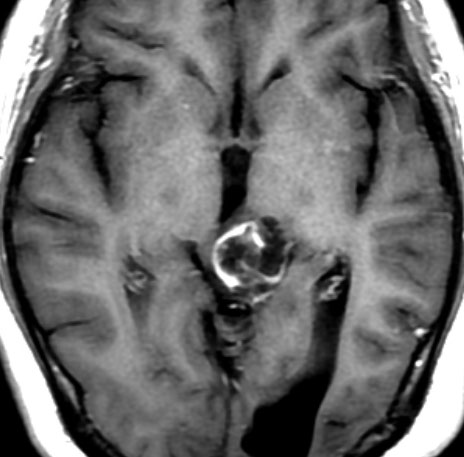

T1強調ガドリニウム増強画像です。15歳の時は腫瘍の半分以上が強くガドリニウム増強されていましたが,この21歳の時の画像では,中心部やや右寄りに増強像が認められるだけです。この性質は,腫瘍が毛様細胞性星細胞腫であることを示しています。

左はT2強調画像,右はFLAIR画像です。中脳視蓋 tectum の中でも上丘が腫瘍化していることが解りますし,松果体は正常の大きさで腫瘍の上に乗っていますから,松果体腫瘍ではないことが解ります。上髄帆にも浸潤しています。